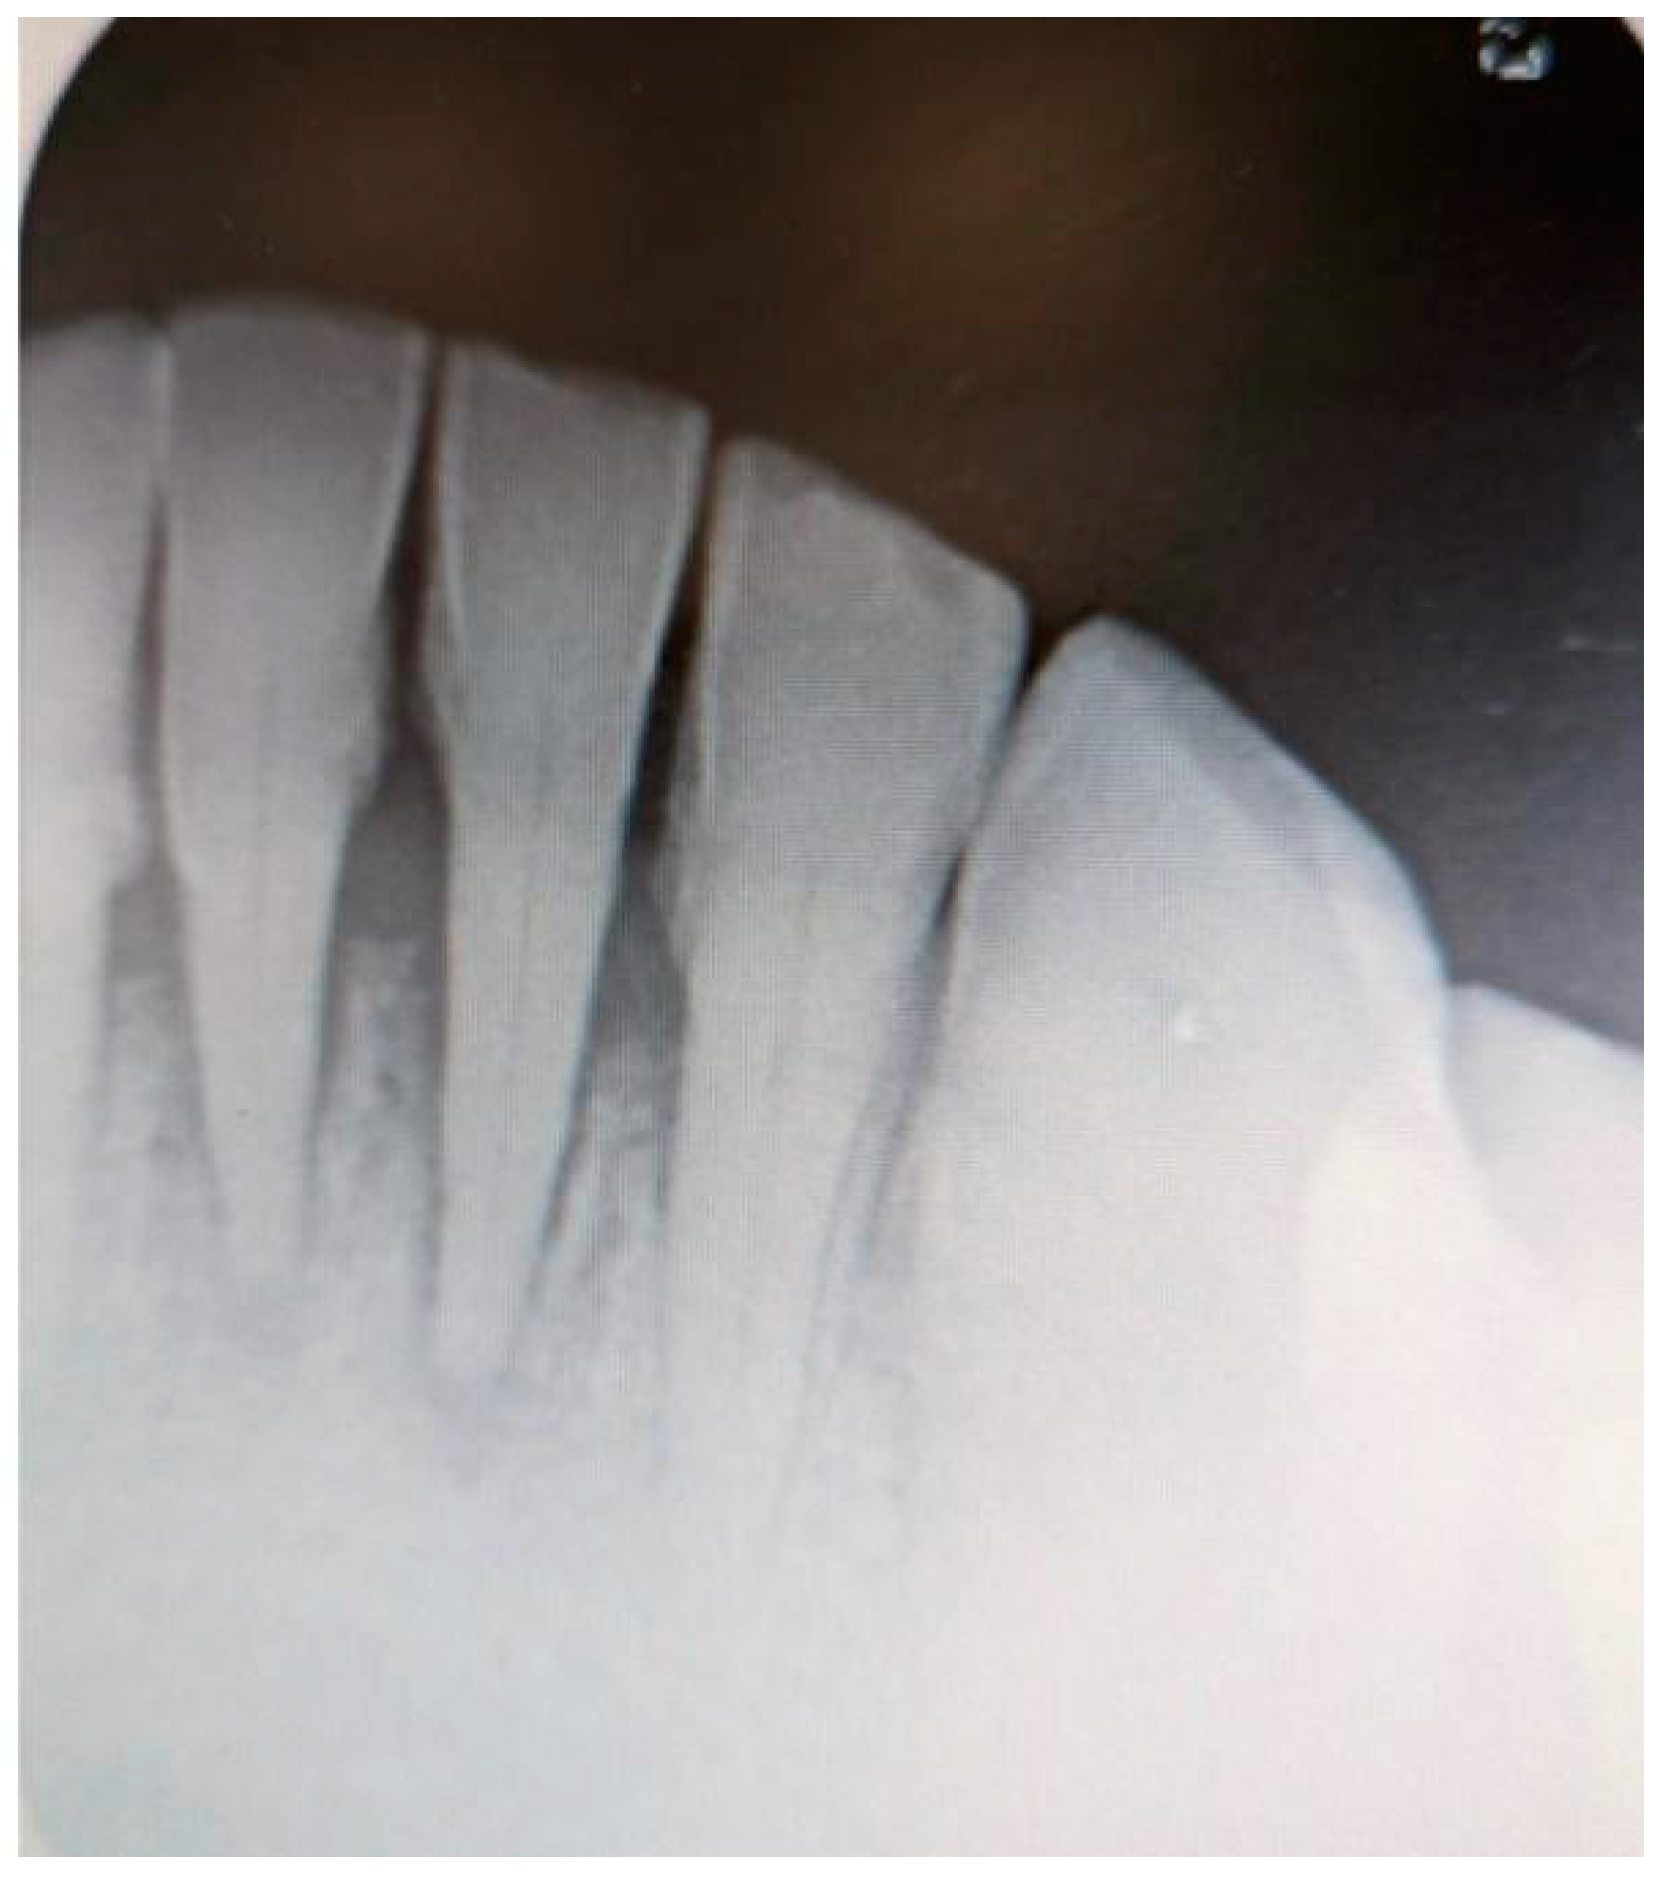

Additionally, digital periapical radiographs of the patient’s maxillary and mandibular incisors were taken to exclude periapical lesions in these areas (Figure 3 and Figure 4).

Pulp vitality tests were conducted on teeth 11, 12, 32, 31, 41, and 42, all of which were found to be vital. No other dental disorders or potential odontogenic infections were identified during the examination.

Figure 4. Digital periapical radiograph of the patient’s mandibular incisors.

Medicina 61 00299 g004